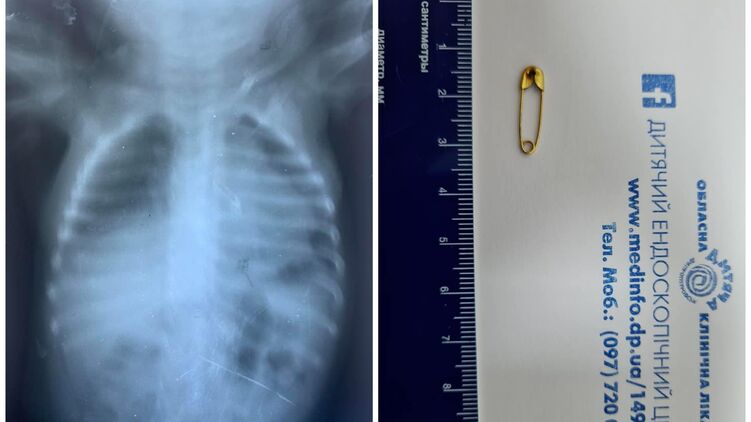

Малыш, которому нет и годика, вдохнул булавку во время игры. Ребенку провели дополнительное обследование. После чего под общим обезболиванием при проведении бронхоскопии извлекли инородное тело.

Отмечается, что в настоящее время ребенок дома в удовлетворительном состоянии.